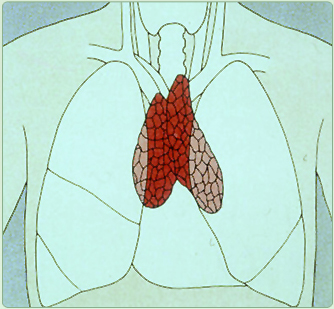

Die Thymusdrüse liegt beim Menschen hinter dem Brustbein, vor dem Herzen und besteht

aus 2 Lappen.